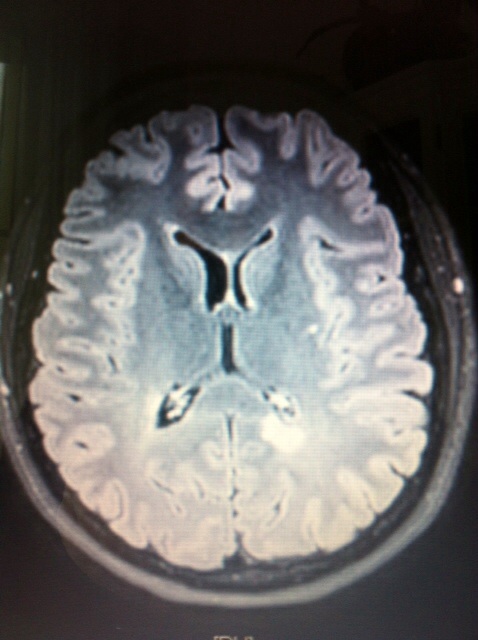

Letzten Montag war Neurotermin. Wir beschlossen ein neues MRI zu machen. Am Dienstag rief das Krankenhaus an und ich hatte einen MRI-Termin für Donnerstag. Es wurde diesmal nur 2x gestochen und der Zugang für das Kontrastmittel war drin. Nach ca. 40min. war ich auch schon wieder fertig. Abends rief mein Neuro auch schon an, um mir mitzuteilen, dass es KEINE VERÄNDERUNG zum letzten MRI gibt. Das bedeutet, seit März 2013 gab es keine neuen Läsionen!!! Jetzt heisst es, weiter so, auch ohne Medikamente!

Bisher habe ich 5 erbsengrosse Schädigungen (rechts Mitte, im Bild) und 2 ca. 2.5cm Durchmesser (unten rechts im Bild). Die Läsionen leuchten weiss in der grauen Hirnmasse.